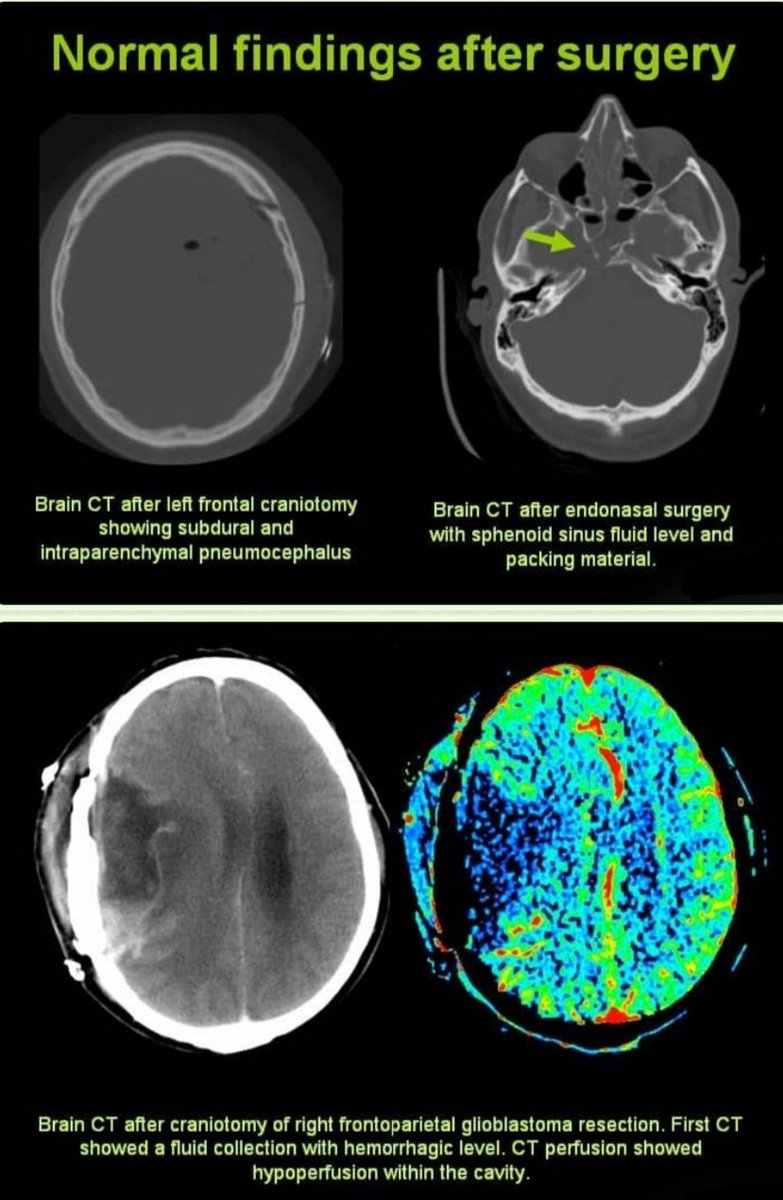

Two additional examples👇👇👇